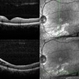

- Xlinked juvenile retinoschisis

- Fundus photograph of a 27-year-old male with x-linked juvenile retinoschisis shows foveal retinoshisis with spokewheel pattern in his left eye.